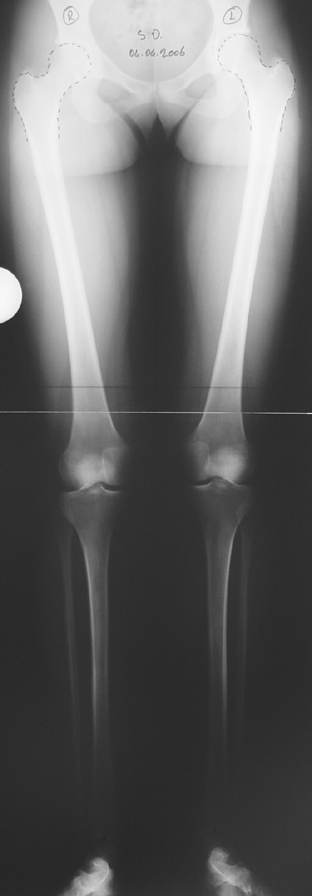

In selected cases, we prefer to use a combination of a unilateral dynamic axial fixator and an interlocked intramedullary nail, in order to protect the length and alignment after the completion of the lengthening procedure. As a prerequisite for this technique, the narowest diameter of the medullary cavity shall be wider than 7 mm and the length of the nail segment distal to the osteotomy site shall be at least 8 cm. after the completion of the lengthening procedure.The intramedullary nail neutralizes shear and bending forces on femur during lengthening, shortens external fixation time, and protects newly formed bone against fractures. In our series, subtrochanteric osteotomy was performed in one case. No varus angulation occured despite the intramedullary nail.

Another complication of lengthening over nail in children is development of secondary coxa valga due to damaging of greater trochanter, which is close to the entry site of the nail. All cases but one in our series were skeletally mature. One case was 12 years old, and no coxa valga deformity was detected at last control. The case is still under control.

The combination of intramedullary anil and dynamic axial external fixator is harder as a technique than Standard Ilizarov applications. However, it is stil appealing due to the following advantages: shortening of the duration of external fixation, protection against refracture, early rehabilitation, gaining maximum range of motion and daily quality of life. These advantages are more important than disadvantages such as increased cost, increased blood loss and potetntial deep infection. All in all, we believe that the technique of femoral lengthening over an intramedullary nail is a safe and reliable method and provides advantages over standard Ilizarov aplications.